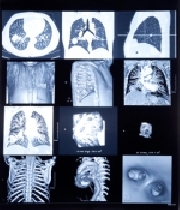

Aktuelle bildgebende Diagnostik der Wirbelsäulenerkrankungen

Wirbelsäulenbeschwerden zählen zuden häufigsten Gründen einer ambulanten Krankenbehandlung. Schätzungen gehen davon aus, dass der Anteil am Patientenaufkommen inorthopädischen Praxen über 50% beträgt. Volkswirtschaftliche Berechnungen geben die in Deutschland jährlich durch Wirbelsäulenschmerzen verursachten Kosten mit bis zu 35 Mrd. Euro an. Daher ist eine effiziente und adäquate Diagnostik zur Beurteilung und Planung weiterführender orthopädischer und unfallchirurgischer Maßnahmen unerlässlich. Diese Arbeit gibt eine Übersicht über die aktuell verfügbaren bildgebenden Verfahren und deren Stellenwert bei der Diagnostik von Wirbelsäulenerkrankungen(s. Tab. 1).

Die Projektionsradiographie (CR) der Wirbelsäule in zwei Ebenen (a.p. undseitliche Projektion) stellt nach wie vor die Standarduntersuchung dar und sollte als initiale Basisdiagnostik erfolgen(s. Tab. 1). Hierauf können die knöchernen Strukturen der Wirbelsäule, die Stellung der einzelnen Wirbelkörper und deren Alignement beurteilt werden. Zielaufnahmen und Spezialaufnahmen, u.a. die des Dens axis, werden zu besseren Beurteilung des kraniozervikalen Überganges mit geöffnetem Mund im a.p. Strahlengang durchgeführt. Zur Beurteilung segmentaler Blockierungen oder Instabilitäten können Funktionsaufnahmen in Retro-und Anteflexion ergänzend durchgeführt werden. Wirbelsäulenganzaufnahmen mit Abbildung der Beckenkämme werden zum Nachweis skoliotischer Fehlhaltungendurchgeführt. Da die CR einem Summationsbild entspricht, können einige Abschnitte der Wirbelsäule durch die sie umgebenden Organe und knöchernen Strukturen häufig nicht in ausreichender diagnostischer Qualität abgebildet werden. Diese Regionenbetreffen vor allem den zervikothorakalen Übergang durch Überlagerung der Schultern sowie die Sakroiliakalgelenke. Zur überlagerungsfreien Darstellung dieser Strukturen eignet sich die CT, die heute vorzugsweise als MDCT durchgeführt wird.

Computertomographie

Die computertomographische (CT-)Untersuchung der Wirbelsäule sollte als dünnschichtiger axialer Rohdatensatz mit einer Primärschichtdicke von 0,5–1,25 mm generiert werden, um für sekundäre Rekonstruktionen die bestmögliche Bildqualität zu gewährleisten. Routinemäßig werden axiale Rekonstruktionenbei knöchernen Fragestellungen mit einem kantenangehobenen Faltungskern, zur Darstellung der Weichteile und der Bandscheiben mit einem glättenden Kernin einer Schichtdicke von 2–3 mm empfohlen. Neben axialen Schnittbildern werden stets zweidimensionale multiplanare Rekonstruktionen (MPR) in sagittalen und koronaren Ebenen sowie beispeziellen Fragestellungen dreidimensionale Rekonstruktionen als „surface shadeddisplay“ (SSD) und „volume rendering“(VRT) angefertigt. Die enorme Innovatio nund breite Verfügbarkeit hat den Einsatz der MDCT in der Akut- und Notfalldiagnostikvon Wirbelsäulenerkrankungen ermöglicht; die Projektionsradiographieals diagnostisches Mittel der Wahl wurde durch sie bereits teilweise abgelöst(s. Tab. 1).